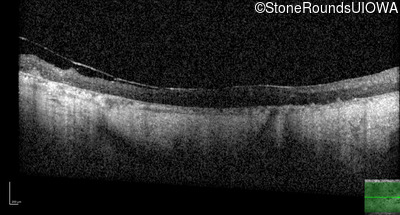

Age at visit: 61 years